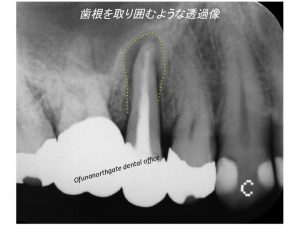

1症例目は、以下の患者様です。

レントゲンをみてみましょう!

早速歯周ポケット検査 と レントゲン写真の撮影を行いました。

問題となる歯は印の歯です。

歯周ポケットは8ミリあり、

出血もあります。

本日の最初に重度歯周病は、歯周ポケットが7ミリ以上と解説しましたので

この歯は、8ミリもありますので

歯周病ということになりますが、

そうではありません。

確かに歯周ポケットは8ミリなのですが、

この歯周ポケットができた原因は、

歯周病細菌による感染症ではなく、

歯が折れたのです。

この歯は神経がない歯でした。

神経のない歯は脆く、通常の噛む力でも折れることが高頻度で起こります。

歯の根が折れることを

歯根破折と言います。

歯根破折の特徴的なレントゲン像をみてみましょう!

歯の根を取り囲むように黒い状態がみれます。

分かりやすいように黒くなっている部分を

黄色線で記載したのが以下です。

このようなレントゲン像を見た場合、

歯根破折を疑います。

患者様には歯根破折の可能性が高いことを説明させていただきました。